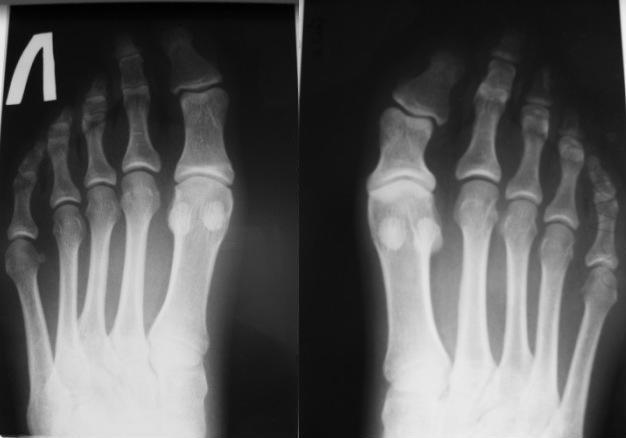

Рентгенограммы прилагаю.

Благодарю за совет. Вот только пациентка считает,что не совсем верно и логично "подгонять" здоровые пальцы на стопе под диспластичный. И в результате получить ещё более проблемную с эстетической точки зрения стопу на 1/2 размера меньше. Считаю эту тактику ошибочной. Думаю, что стоит остановиться на варианте коррегирующей остеотомии фаланги с одномоментной кстной пластикой. Выполнив операцию, постараюсь ознакомить Вас с результатом. Благодарю за помощь. С уважением Евгений

Оптимально корригирующая "плюс" остеотомия с костной аутопластикой. Фиксировать тонкими спицами.

Что касается 2 пальца -так называемый "греческий" тип стопы - один из вариантов нормы. Его укорачивают при HALLUX VALGUS с сочатании с молоткообразной деформацией 2 пальца в зависимости от степени удлинения. Здесь молоткообразной деформации нет. Трогать по-моему не стоит.